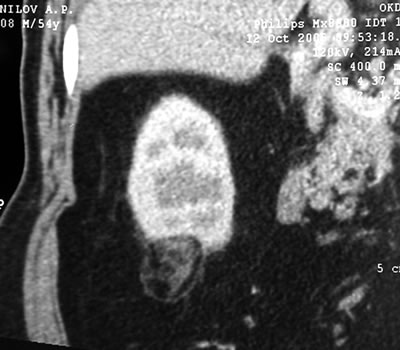

Мониторинг

(7 месяцев)

КТ легких – норма.

УЗИ брюшной полости – метастазов в печени нет. |

Спиральная

компьютерая томография (СКТ)

в нижнем сегменте образование

30х34х40 мм, располагающееся экстраренально, структура

неоднородна с наличием компонентов жировой плотности

по периферии, а также мягкотканой части.

|

в паранефральной клетчатке

- умеренные фиброзные изменения.